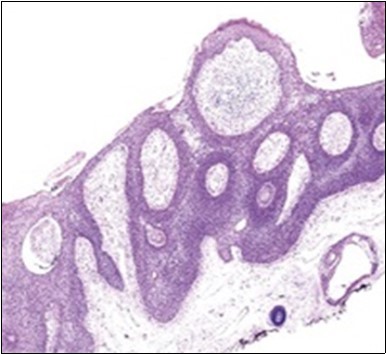

The neoplasm is composed of lobules of aberrant epithelial cells configured in cords with incrimination of the dermis and epidermis.. Malignant cells congregate within the epidermis or infiltrate the dermis, especially in the primary tumour. Tumour cells within tumour aggregates display a well demarcated cellular outline and appear distinct from encompassing squamous cells. Numerous tumour cell clusters demonstrate a cystic lumen. Prominent epidermal acanthosis is discerned on account of tumour cell proliferation 6, 7.

Granular arrangement of malignant cells and intercellular bridges are conspicuous with the demonstration of nuclear atypia, pleomorphism, prominent mitosis and tumour necrosis. A peripheral palisade is discernible within the cellular aggregates. Mitotic figures are common and can be quantified as up to 12 mitosis/ high power field. Tumour differentiation can prominently be of the ductal category with the demonstration of intra-cytoplasmic lumina. Comedo type tumour necrosis is evident along with foci of squamous differentiation The neoplasm is reactive to periodic acid Schiff ‘s (PAS) stain. (Figure 1, Figure 2, Figure 3, Figure 4, Figure 5, Figure 6, Figure 7, Figure 8, Figure 9, Figure 10, Figure 11, Figure 12, Figure 13.

Figure 2.Epidermal projections lined with atypical and malignant epithelial cells in eccrine porocarcinoma (14).